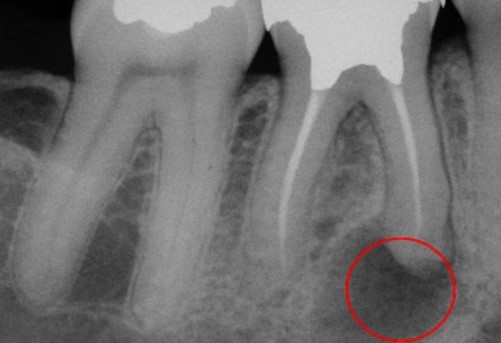

Гранулемы редко превышают 1 см в диаметре. Небольшие гранулемы можно различить только при рентгенологическом исследовании, ортопантомограмме или компьютерной томографии.

- компьютерная томография. На рентгене гранулема выглядит как округлое затемненное пятно с четкими контурами.

Гранулему дифференцируют с кистами, новообразованиями, в том числе костной опухолью. При необходимости требуются вспомогательные методы обследования.